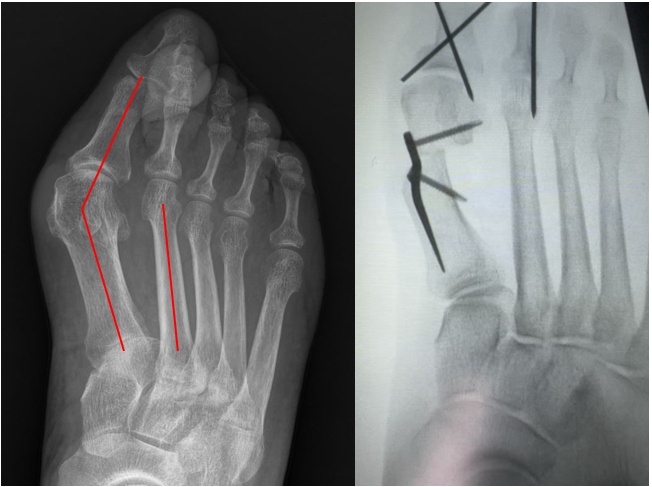

图注:术后效果:足部轴线恢复正常,叠趾畸形得到彻底纠正,外观改善显著

图注:手术原理示意:通过微小切口进行截骨,并将髓内板精准植入以重建足部力学结构

图注:术前 vs 术后的 X 光影像对比:术后拇外翻角(HVA)和第1、2跖骨间夹角(IMA)矫形至正常范围